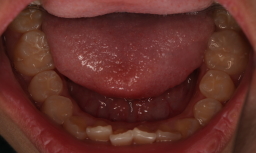

上顎の歯 歯磨きはあんまりしないので、軽度の歯周炎が ありますが、 フッ素塗布とフッ素飲料とシーラントでむし歯ゼロです。 2015年04月現在 |

|

| 下顎の歯 歯磨きはあんまりしないので、軽度の歯周炎が ありますが、 フッ素塗布とフッ素飲料とシーラントでむし歯ゼロです。 2015年04月現在 |